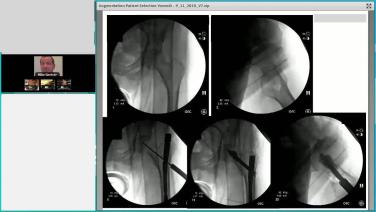

Augmenting Geriatric Hip Fractures: Reduction & Augmentation Techniques with Greg Osgood, MD

Augmenting Geriatric Hip Fractures: Logical Indications Through Case Examples with Michael Gardner, MD